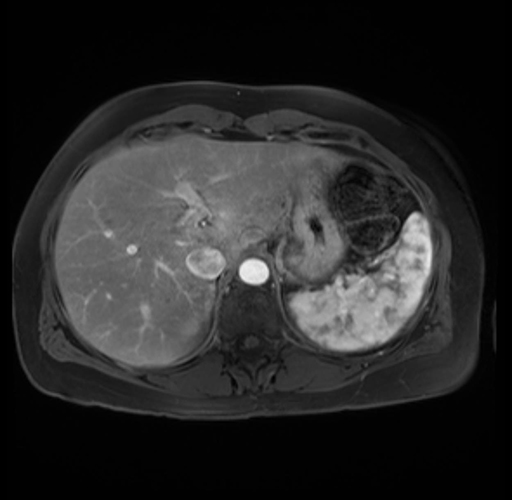

Imaging Analysis

Look through the patient's CT scan to identify any areas of concern for the necessary procedure.

Based on your CT findings, which issue(s) are present and would give reason for "planned slowing down moment(s)" in this case?